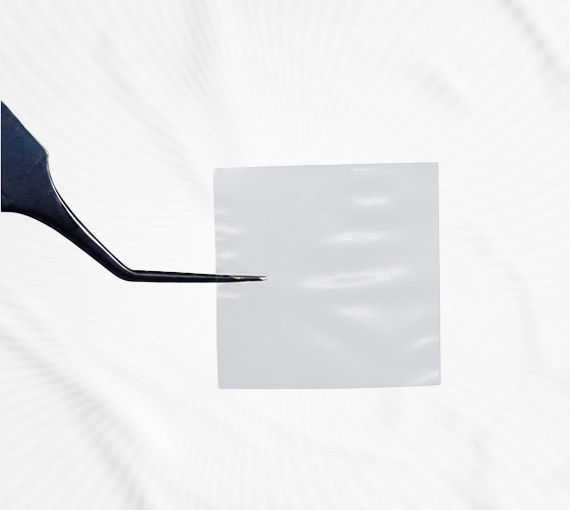

Kronikleşmiş yaralar; özellikle diyabetik ayak yaraları, venöz ülserler ve bası yaraları gibi zor iyileşen lezyonlar, hastaların günlük yaşamını olumsuz etkileyerek ciddi sağlık sorunlarına yol açabilmektedir. Bu tür yaralar, zamanla enfeksiyon riskini artırabilir, tedavi sürecini uzatabilir ve yaşam kalitesinde belirgin bir düşüşe neden olabilir. Amniyotik membran tedavisi, iyileşme süreci yavaşlamış veya duraksamış yaralar için geliştirilmiş; güvenli, etkili ve hasta konforunu ön planda tutan güncel bir medikal uygulamadır. İzmir’de bulunan merkezimizde uygulanan bu biyolojik tedavi yöntemi, yara yüzeyine uygulanan amniyotik membranın içerdiği doğal büyüme faktörleri sayesinde doku yenilenmesini desteklerken, iyileşme sürecine aktif katkı sağlar. Yumuşak yapısı ve biyouyumlu özelliği sayesinde hastalar için konforlu ve destekleyici bir tedavi süreci sunar.

Amniyotik membran, klasik yara bakımının ötesine geçerek yalnızca yüzeysel iyileşmeyi değil, hücresel onarım ve biyolojik dengeyi de destekleyen aşağıdaki önemli avantajları sağlar;

Doğal bariyer etkisi sayesinde yara yüzeyini koruyarak mikrobiyal kontaminasyon riskinin azaltılmasına yardımcı olur.

İçeriğindeki büyüme faktörleri ve biyolojik proteinler, yara iyileşmesini tetikleyerek doku rejenerasyon sürecini destekler.

Amniyotik membran uygulaması hassas dokularla uyumlu yapısı sayesinde hastalar için ağrı veya rahatsızlık oluşturmaz.

Nem dengesini koruyarak kronik yaralarda sağlıklı ve iyileşmeye elverişli bir yara ortamı oluşturulmasına katkı sağlar.